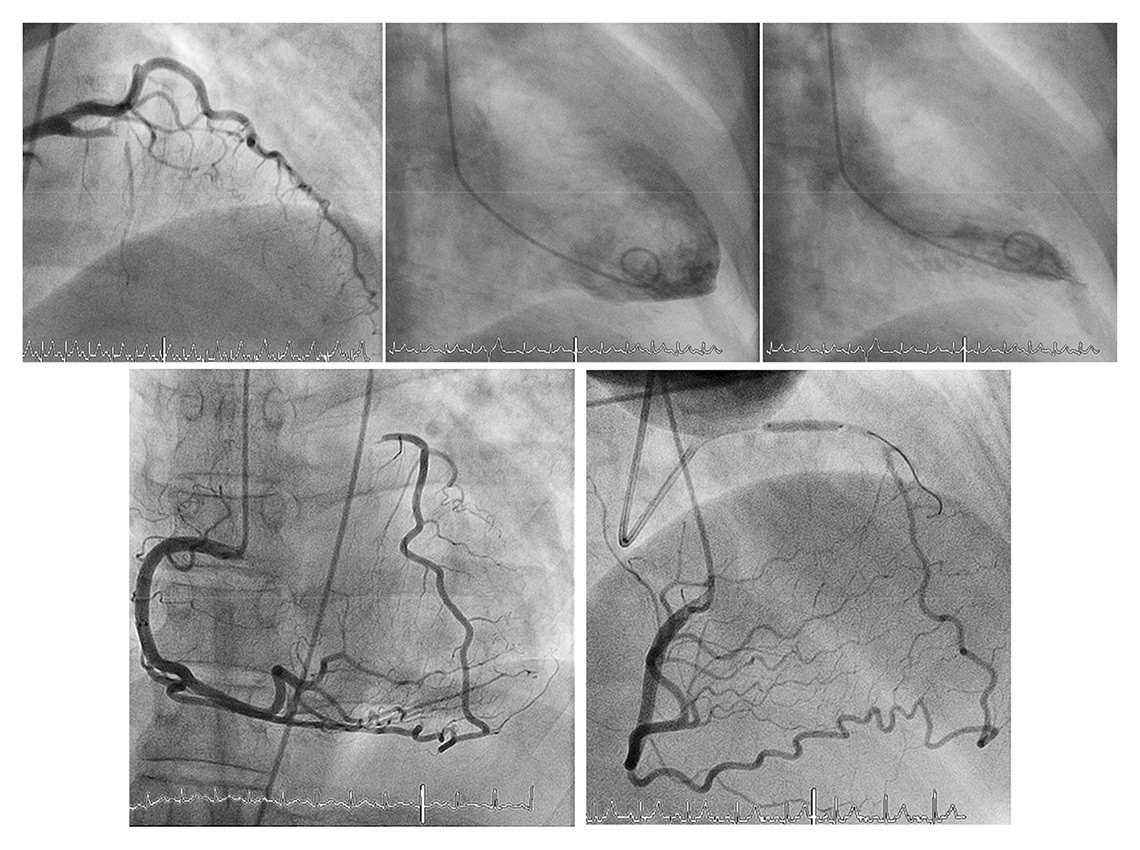

Figure 6

Completely normal left ventricular angiogram (top middle and right) due to extensive collateral supply of the proximally occluded left anterior descending artery via apical branch and septal collateral by the right coronary artery (bottom). Functional assessment is performed by balloon occlusion after recanalization of the chronic total occlusion (bottom right).

(Data from Seiler C. Assessment and impact of the human coronary collateral circulation on myocardial ischemia and outcome. Circ Cardiovasc Interv. 2013;6:719–28 [86], with permission.)

With chronic ischaemia, a (further) decline in left ventricular function results from hibernating and stunned myocardium [118]. Here, the not infrequently encountered case of completely normal ventricular function in the presence of a CTO exemplifies the protective effect of the coronary collateral network (fig. 6) [24, 72]. Furthermore, it has been shown that regional LV function is directly related to the amount of collateral flow during both acute and chronic coronary occlusion [24, 119]. Concerning postinfarction sequelae, the relevant protective role of collaterals has been shown to result in a reduction of postinfarct ventricular dilatation and less ventricular aneurysm formation [7].